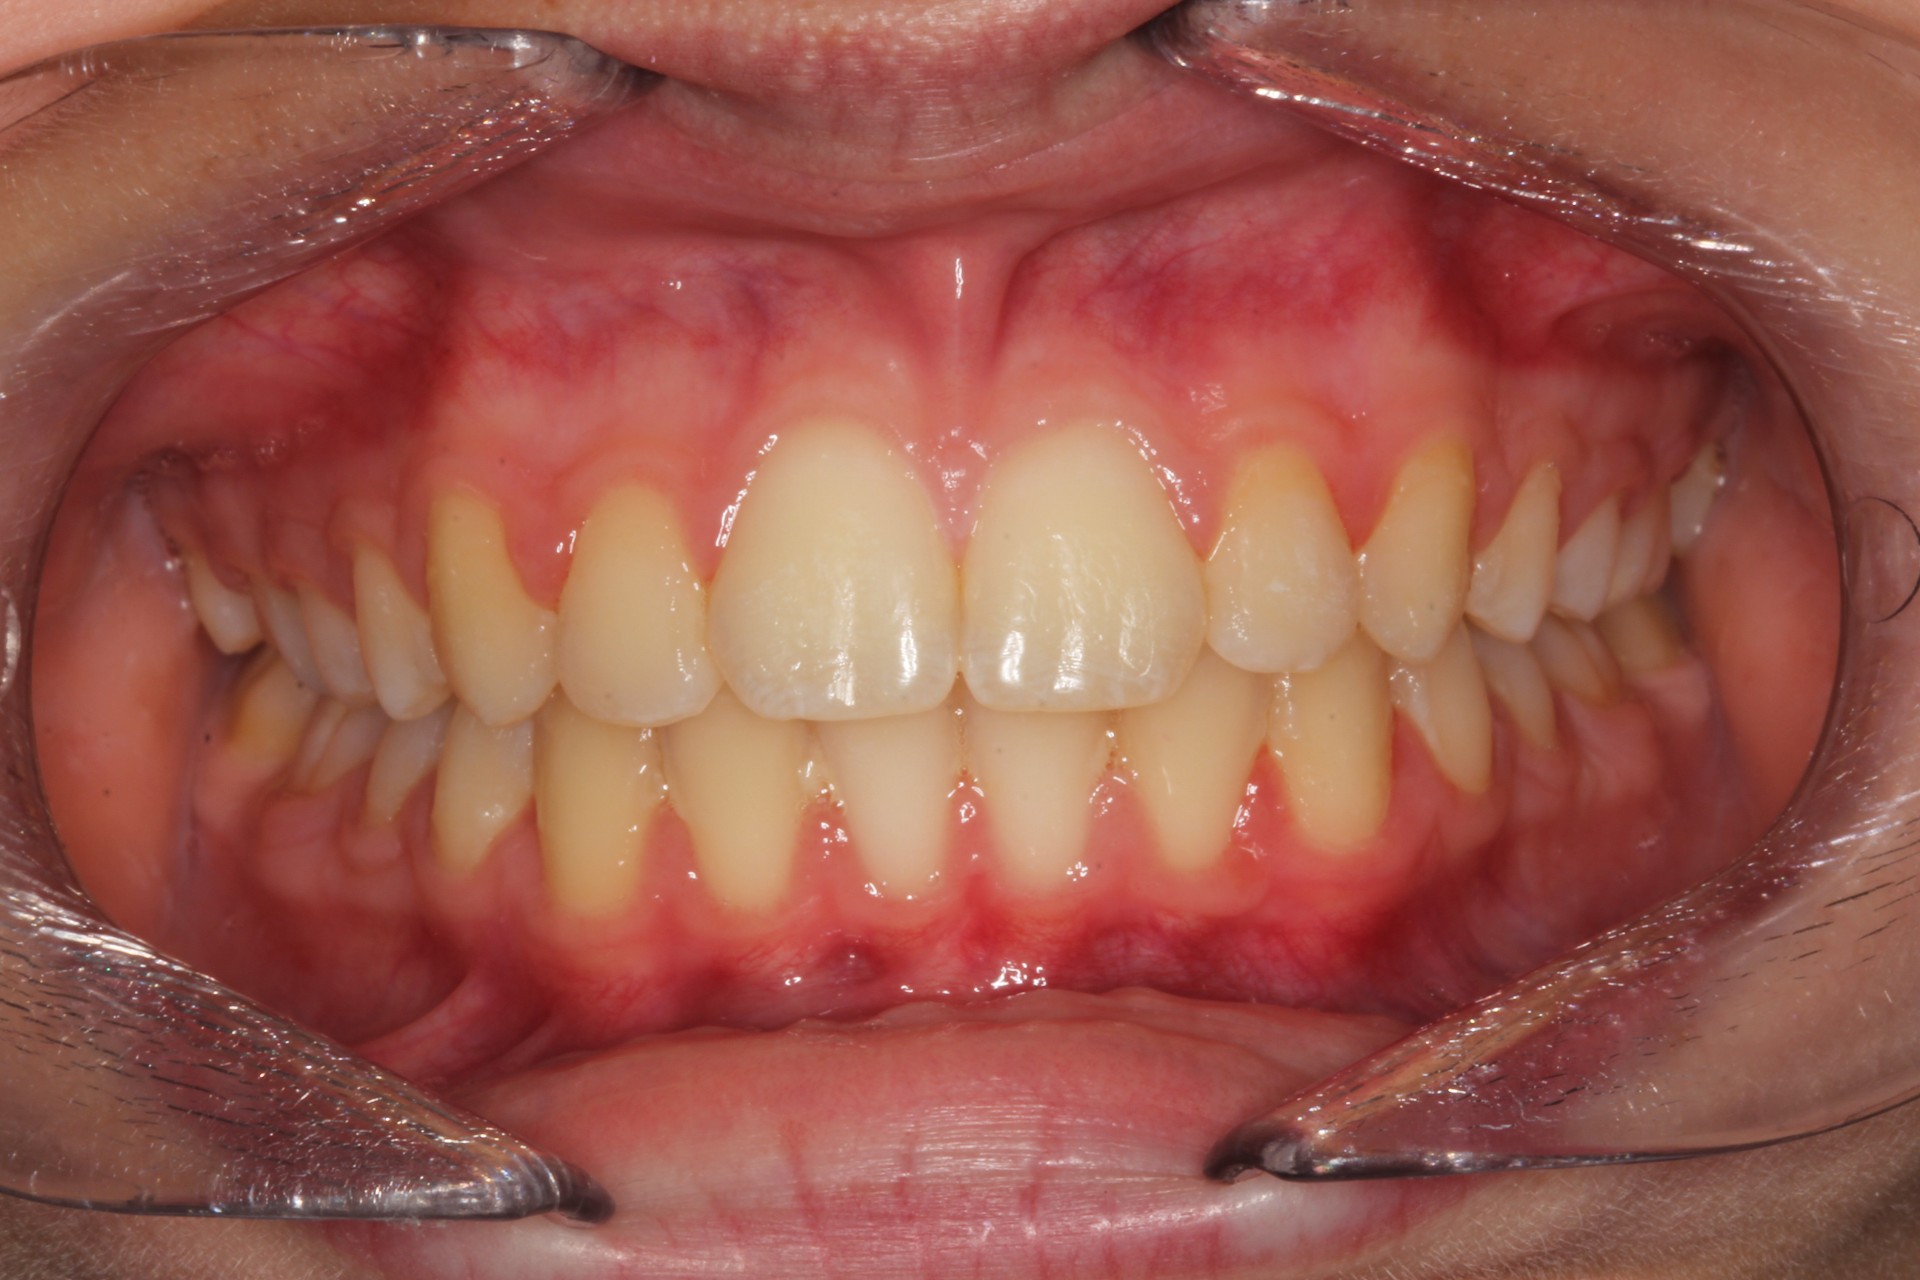

Protruding front teeth with midline diastema – Child case